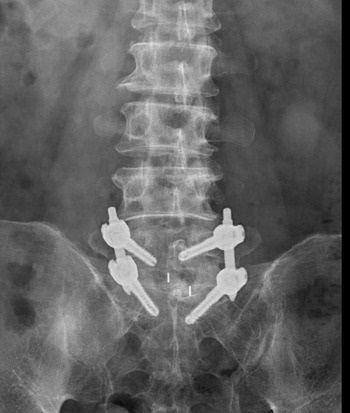

影像檢查顯示,張先生的第五節腰椎椎弓骨折合併脊椎解離。洪祥益主任表示,這類病人多半表現為腰痠背痛、久坐久站困難,通常可先藥物治療觀察,但相較於其他類似問題的病人,張先生疼痛異常明顯,手術中發現脊椎關節內長滿痛風石,這些痛風石如白色黏稠物般,附著在神經與關節縫隙間,若不清乾淨,就會持續引發神經發炎與疼痛,甚至比坐骨神經痛更強烈。團隊透過顯微鏡,在不傷及神經的情況下,仔細將痛風石刮除清理,再以微創固定融合手術完成治療。

右圖:洪祥益主任與團隊透過顯微鏡,在不傷及神經的情況下,仔細將痛風石刮除清理,再以微創固定融合手術完成治療。